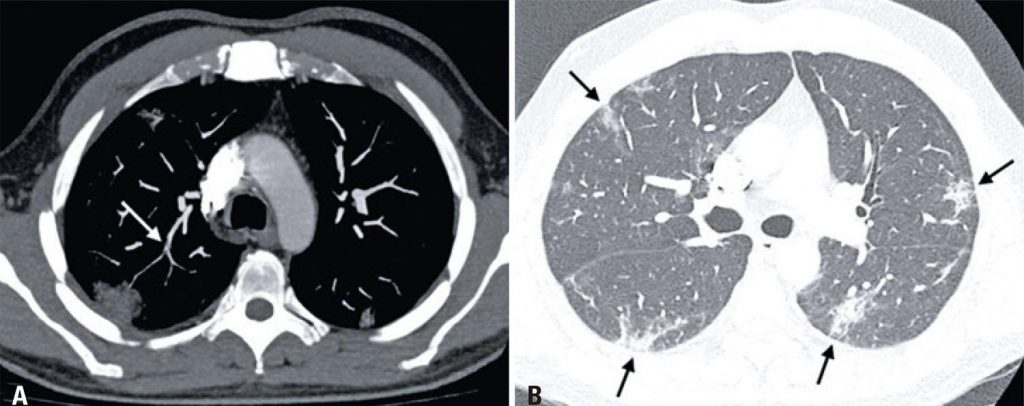

A 49-year-old man who underwent a computed tomography pulmonary angiography (CTPA) due to a worsening of dyspnea, newly onset of chest pain and D-dimer elevation (711ng/dL) on the seventh day of hospitalization. A filling defect was observed on the segmental artery branch in the right superior lobe, a compatible finding with pulmonary embolism ( ), as well as typical changes caused by coronavirus pneumonia ( ). ( , )